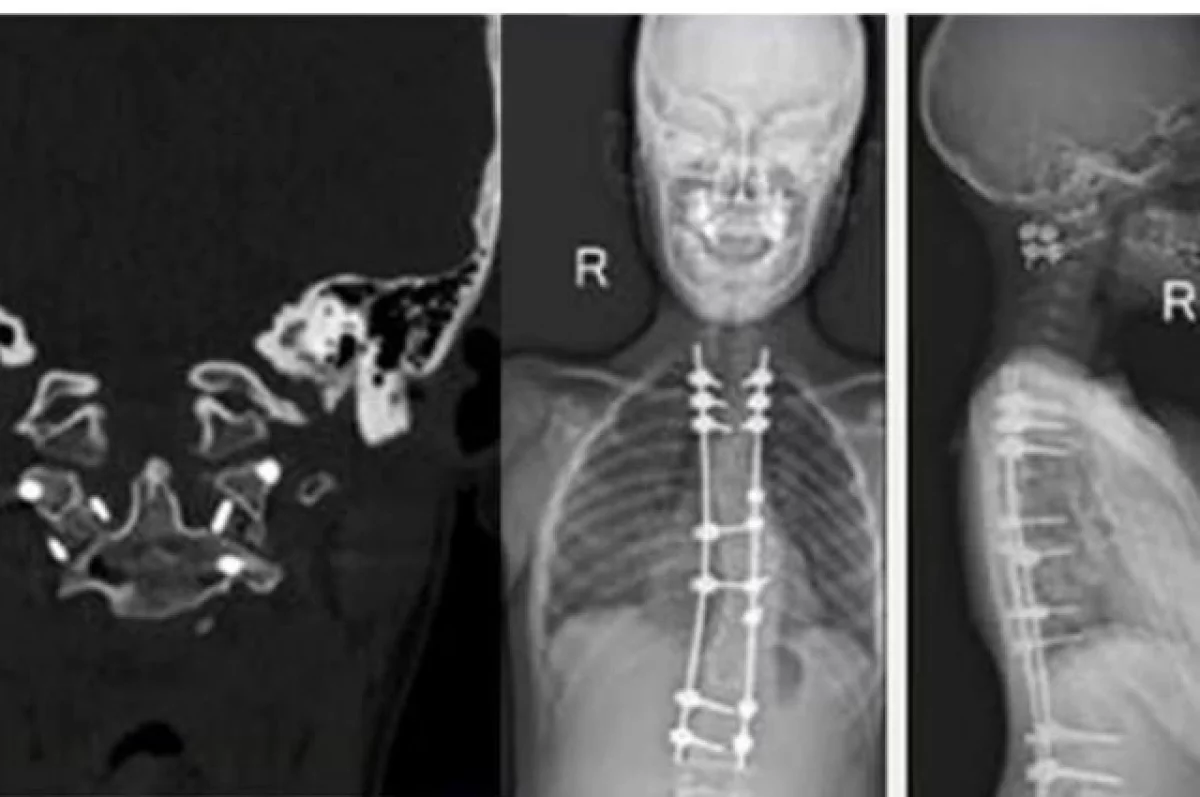

После несчастного случая подростка экстренно доставили в клинику центра. Врачи провели сложнейшую операцию на шейном отделе позвоночника: устранили сдавление спинного мозга и выполнили стабилизацию позвонков.

Это уже не первый раз, когда в центре помогают этому пациенту — ранее врачи здесь же успешно исправили у него тяжелую деформацию позвоночника.